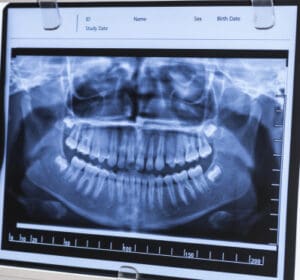

As a team, we want your visit to the dentist to be stress-free and beneficial for you to make the best decisions for your health. Each type of technology we use is for different purposes. For example, during your initial visit, you may see us capture images of your teeth with digital X-rays to diagnose problems and develop a personalized treatment plan to enhance your smile. Our Rockville dentist and team members are trained to perform with these tools to help you receive the care you need.